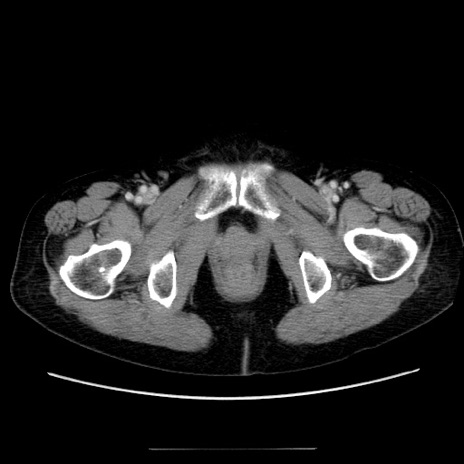

冠状断像

【症例】70歳代女性

【主訴】お腹が張る

【現病歴】1週間くらい前から腹部膨満の自覚あり。昨日夜から増悪したため、本日救急外来受診。

【身体所見】意識清明、BT 36.5℃、BP 165/106mmHg、HR 80bpm、SpO2 98%、腹部:膨満、軟、自発痛・圧痛なし、触診にて不快感あり、腸蠕動音:減弱

【データ】WBC 12600、CRP 1.04